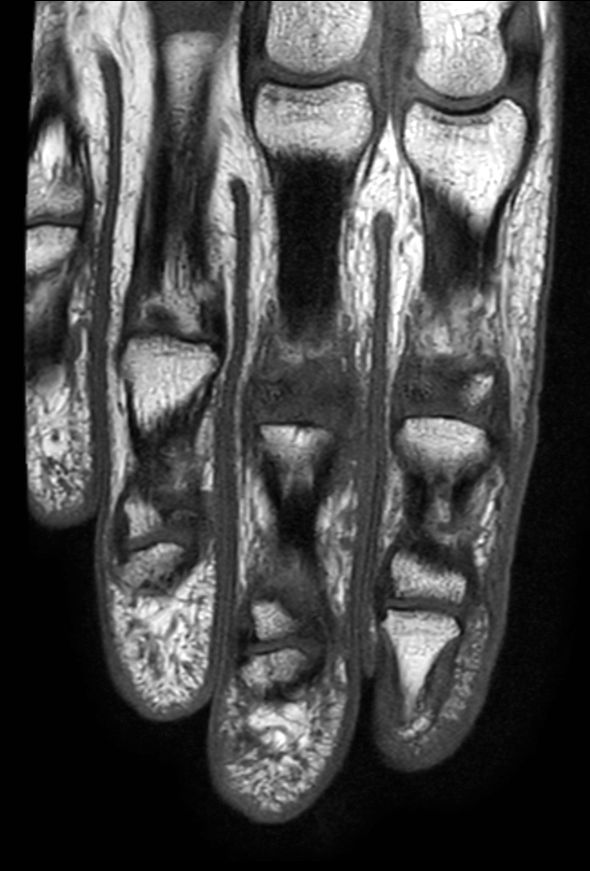

Coronal T2w TSE mDIXON XD